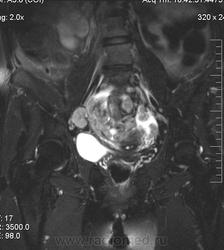

в-целом, cогласен. Карциноматоз тоже есть. Видится еще диффузный аденомиоз матки (задней стенки).

Мне кажется, что есть инфильтрация и передней стенки прямой кишки.